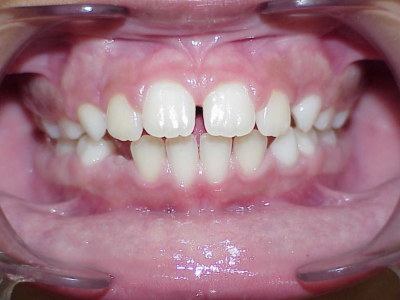

Voor behandeling

Leeftijd bij aanvang: 9 jaar

7-13 maanden: Twinblock